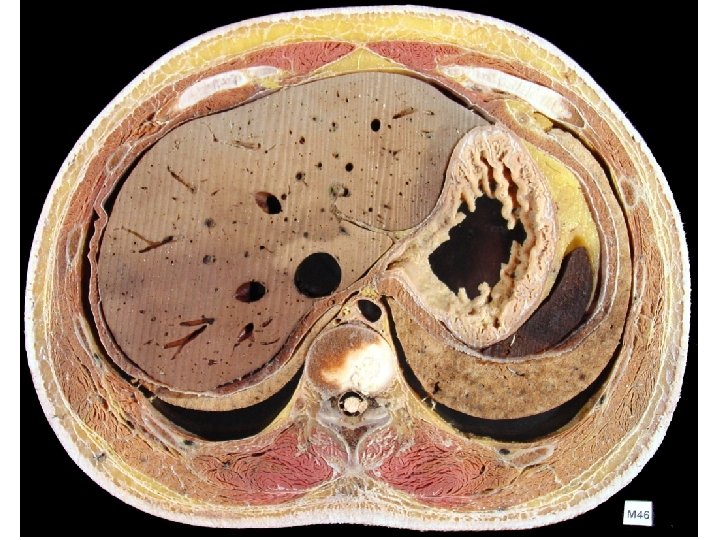

组成composition 消化管Digestive tube • 口腔 Mouth • 咽 Pharynx • 食管 Esophagus • 胃 Stomach • 小肠Small intestine Superior digestive tube 上消化道 十二指肠 Duodenum 空肠 Jejunum 回肠 Ileum Inferior digestive tube 下消化道 • 大肠Large intestine 消化腺Digestive glands • • • 大唾液腺Major salivary glands 肝Liver 胰Pancreas Function: ingestion, digestion, absorption, egesting

Mouth Major salivary glands Pharynx Esophagus Stomach Liver Pancreas Duodenum Large intestine Ileum Jejunum